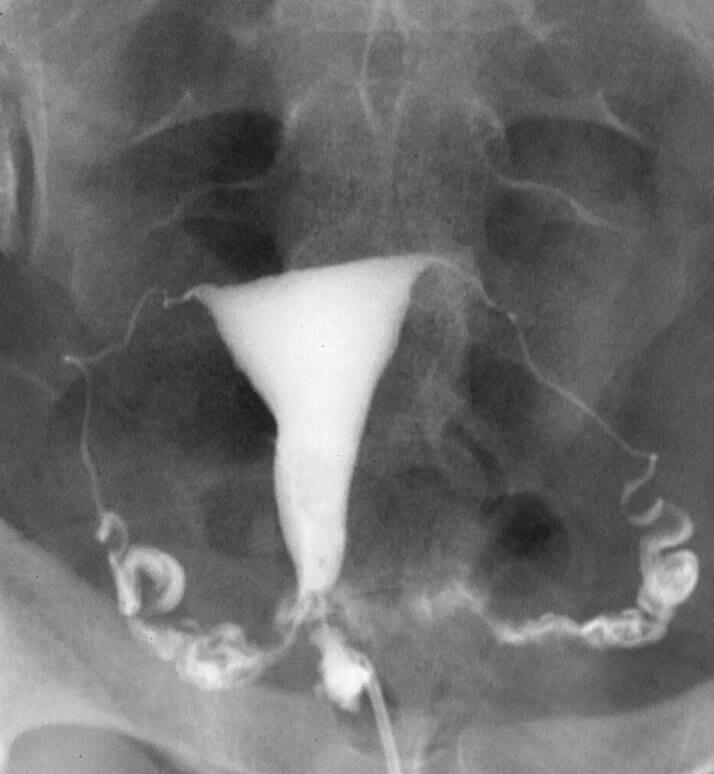

Fluroscopic

Fluroscopic procedure

Fluoroscopy procedures are medical imaging tests that use X-rays to produce real-time, moving images of the inside of the body.